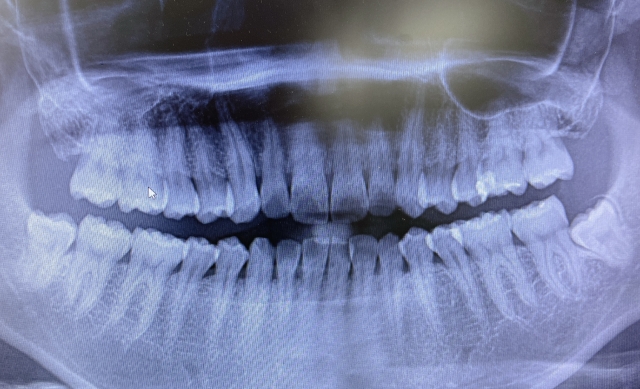

歯科医はあなたの歯を検査し、その部分のX線写真を撮ります。これは、あなたの歯にどのような治療が最適かを判断するのに役立ちます。

親知らずやその周囲に痛みや不快感がある場合は、歯科医に電話して予約を取りましょう。この領域は見にくい場合があります。痛みの原因を調べるには、歯科検査とレントゲン検査が必要になる場合があります。